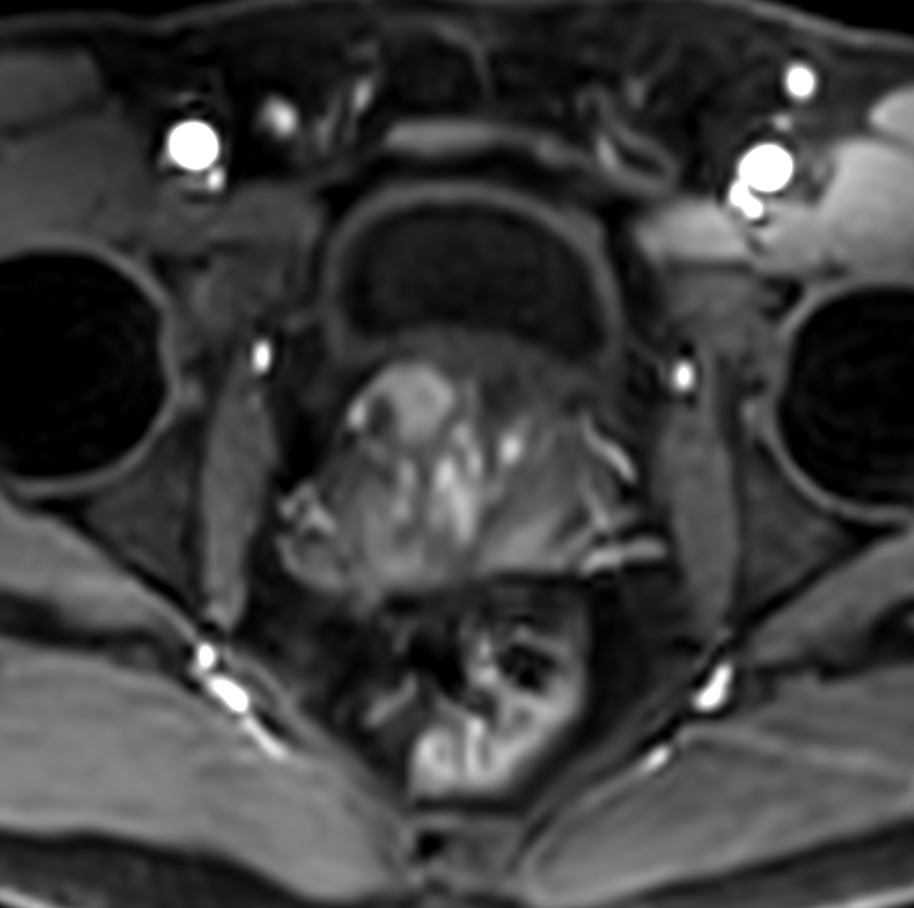

Axial dynamic T1w mDIXON XD - Permeability 34 sec

-

Axial dynamic T1w mDIXON XD - Permeability 53 sec